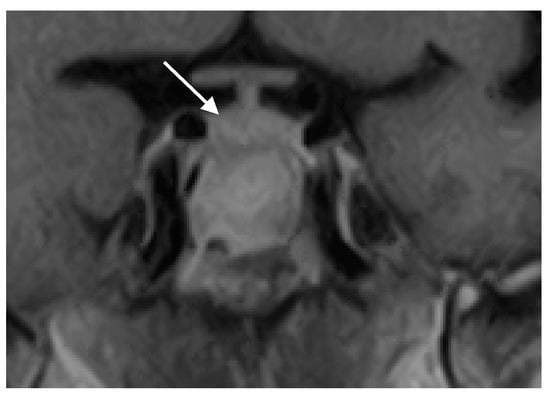

A 56-year-old immunocompetent female with no significant medical history presented with nasal congestion, headache, visual disturbances, and bitemporal hemianopia. Sellar magnetic resonance imaging (MRI) revealed a giant mass in the sphenoid sinus and clival region, accompanied by bone destruction and extension into the sellar region and surrounding structures (supra-, infra-, retro-, and pre-sellar regions; Figure 1a,b). The pituitary gland was displaced superiorly, prompting referral to a neurosurgeon and endocrinologist.

Figure 1. (a) Coronal and (b) sagital MRI scans of the sellar region before the transphenoidal operation showing giant hyperintense (on T1-weighted sequences) lesion in the sellar region (white arrows), with a thin rim of enhancement propagating in all directions (supra-, infra-, retro- and pre-sellar). The pituitary gland was displaced superiorly (asterix).